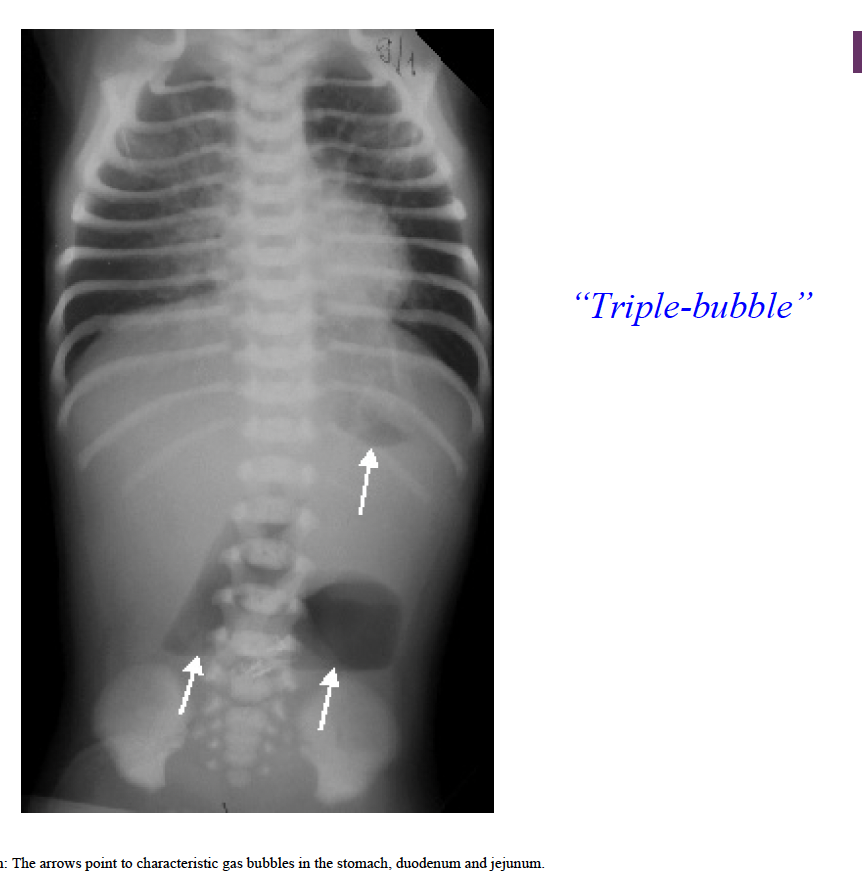

Q

What might cause triple bubble sign?

A

Jejunal atresia